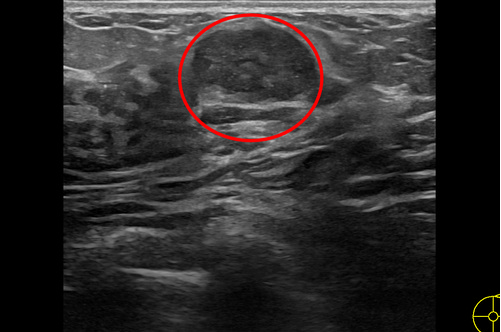

「年輕女性做自我乳房觸檢時所摸到的腫塊,大部分為良性的乳房腫瘤,其中以乳房纖維瘤最常見。」張群明主任表示,乳房纖維瘤是從乳房小葉組織長出並混合上皮與間質組織增生的腫瘤,常見於14 到35 歲年輕女性,發生率約10-20%;纖維瘤摸起來較平滑,有時會有輕微的壓痛,在超音波影像顯示上,是邊界清楚的圓形或橢圓形的腫瘤。

左圖:花蓮慈院乳房醫學中心主任張群明表示,良性的乳房腫瘤,其中以乳房纖維瘤最常見,在超音波影像顯示上,是邊界清楚的圓形或橢圓形的腫瘤。